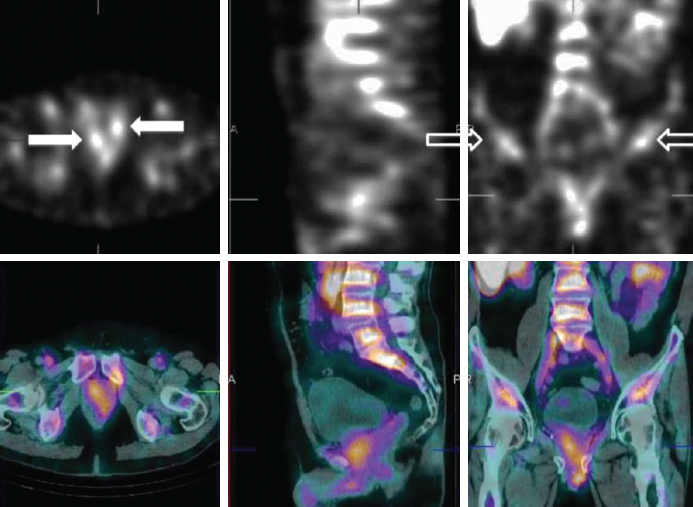

На рис. 5 и 6 представлены сцинтиграммы результатов КИ с 99mTc-PSMA, полученные методом ОФЭКТ/КТ с высокой диагностической эффективностью при визуализации метастатического РПЖ [24].

Рис. 5. Проекция максимальной интенсивности (справа) и совмещённые с КТ (слева) 99m Tc-HYNIC-PSMA ОФЭКТ/CT изображения пациента 59 лет, ранее перенёсшего радикальную простатэктомию, через 2 часа после введения дозы 740 МБк. Были обнаружены множественные метастазы в лимфатические узлы (обозначены стрелкой), а в левом надключичном лимфатическом узле максимальное отношение опухоли к фону составляет 9,2 / Fig. 5. Maximum intensity projection (right) and 99m Tc-HYNIC-PSMA SPECT/CT superimposed with CT (left) images of a 59-year-old patient who had previously undergone radical prostatectomy, 2 hours after a dose of 740 MBk. Multiple lymph node metastases were found (indicated by an arrow), and in the left supraclavicular lymph node, the maximum tumor-to-background ratio is 9.2

Рис. 6. 99mTc-PSMA: два очага активности в малом тазу (белые стрелки); неспецифическое поглощение (контурные стрелки); точная локализация очагов на совмещённых ОФЭКТ/КТ изображениях (нижний ряд) / Fig. 6. 99mTc-PSMA: two foci of activity in the small pelvis (white arrows); nonspecific uptake (outline arrows); exact localization of lesions on combined SPECT/CT images (bottom row)